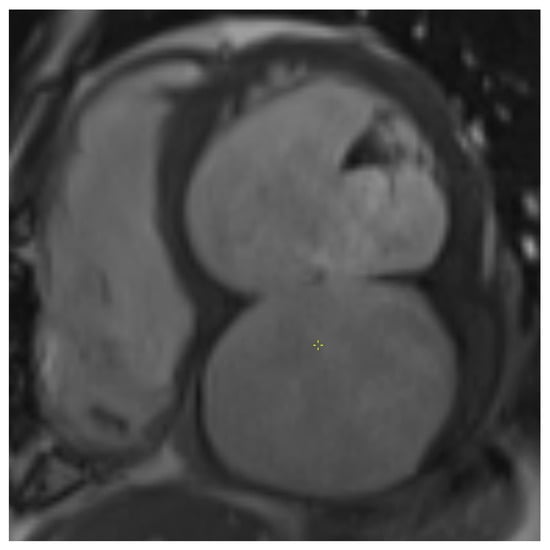

Preoperative TTE showed a moderately dilated LV with a biplane Simpson-derived ejection fraction of 31%. A giant pseudoaneurysm was identified, communicating with the true LV cavity through a broad neck, and containing a mural thrombus. No recurrent pericardial effusion was seen. Additionally, severe functional MR and TR were observed, due to systolic leaflet restriction and annular dilatation. A computed tomography angiography (CTA) illustrated an impressive LV pseudoaneurysm measuring 12.5 × 11.6 × 8.0 cm (Figure 2 and Figure 3).

Figure 3. Short-axis cine image of transmural inferior wall infarction with basal inferior defect and pseudoaneurysm centered below LV and LA.